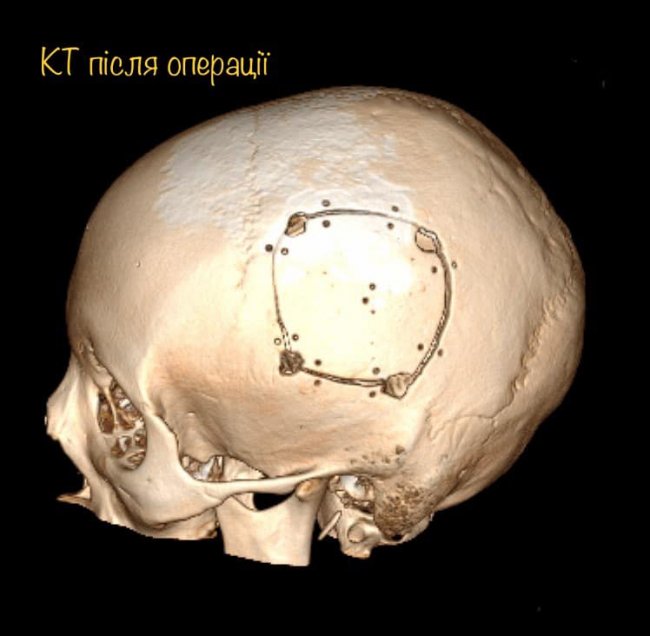

Показами до такого виду втручання було розташування проблемної ділянки в головному мозку (пухлина з крововиливом) близько до функціонально важливих зон мозку (тих ділянок, які дають можливість рухати кінцівками, відчувати, і основне - розмовляти).